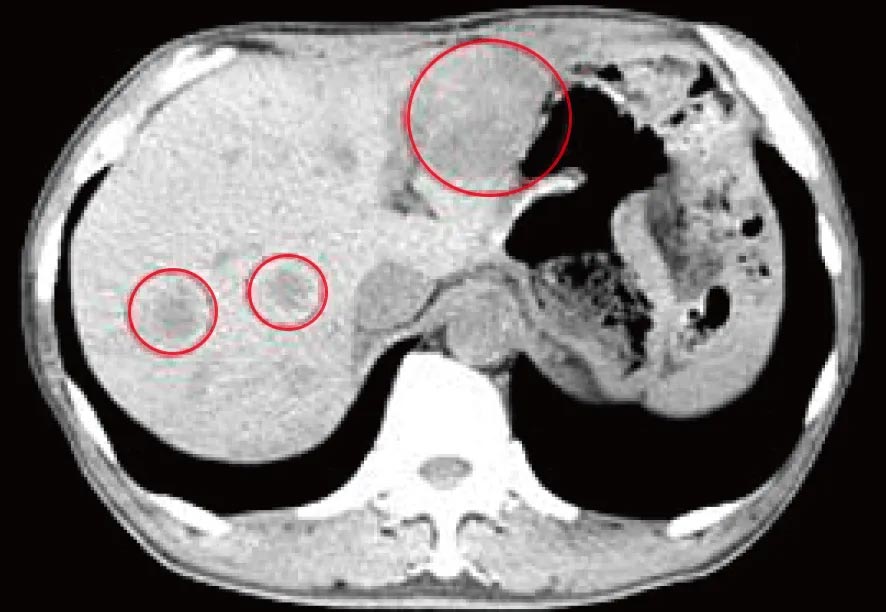

治療前のCT検査結果

肝臓に広がる多発性の肝転移病巣(赤マルで囲んだ3カ所)が認められました。